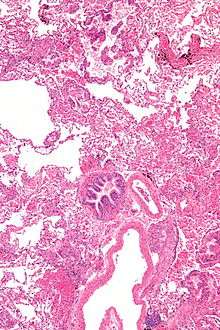

Pathology

Grossly, LAM lungs are enlarged and diffusely cystic, with dilated air spaces as large as several centimeters in diameter.[89][90] Microscopic examination of the lung reveals foci of smooth muscle-like cell infiltration of the lung parenchyma, airways, lymphatics, and blood vessels associated with areas of thin-walled cystic change. LAM lesions often contain an abundance of lymphatic channels, forming an anastomosing meshwork of slit-like spaces lined by endothelial cells. LAM cells generally expand interstitial spaces without violating tissue planes but have been observed to invade the airways, the pulmonary artery, the diaphragm, aorta, and retroperitoneal fat, to destroy bronchial cartilage and arteriolar walls, and to occlude the lumen of pulmonary arterioles.[89]

There are two major cell morphologies in the LAM lesion: small spindle-shaped cells and cuboidal epithelioid cells.[91] LAM cells stain positively for smooth muscle actin, vimentin, desmin, and, often, estrogen and progesterone receptors. The cuboidal cells within LAM lesions also react with a monoclonal antibody called HMB-45, developed against the premelanosomal protein gp100, an enzyme in the melanogenesis pathway.[91] This immunohistochemical marker is very useful diagnostically, because other smooth muscle–predominant lesions in the lung do not react with the antibody.[92] The spindle-shaped cells of the LAM lesion are more frequently proliferating cell nuclear antigenpositive than the cuboidal cells, consistent with a proliferative phenotype.[91] Compared with cigar-shaped normal smooth muscle cells, spindle-shaped LAM cells contain less abundant cytoplasm and are less eosinophilic. Estrogen and progesterone receptors are also present in LAM lesions,[93][94][95] but not in adjacent normal lung tissue.[96] LAM lesions express lymphatic markers LYVE-1, PROX1, podoplanin and VEGFR-3. The smooth muscle–like cells of AMLs are morphologically and immunohistochemically similar to LAM cells, including reactivity with antibodies directed against actin, desmin, vimentin, and HMB-45 as well as estrogen and progesterone receptors.[97][98] Unlike the dilated air spaces in emphysema, the cystic spaces found in LAM may be partially lined with hyperplastic type II cells.[99]